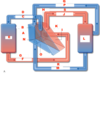

Label A-S

A.) Right pump

B.) Right Atrium

C.) Deoxygenated blood

D.) Pulmonary arteries

E.) Lungs

F.) Oxygenated blood

G.) Pulmonary veins

H.) Left atrium

I.) Left atrium

J.) oxygenated blood in aorta

K.) Left pump

L.) Body

M.) Deoxygenated blood in inferior vena cava

N.) valve

O.) right ventricle

P.) deoxygenated blood in superior vena cava

Q.) Superior vena cava

R.) inferior vena cava

S.) aorta

Trace the blood flow in the circulatory system beginning with blood from the body to the heart.

- ) From the body, deoxygenated blood (venous return) flows through the superior and inferior vena cava in to the right atrium.

- ) From the right atrium, the deoxygenated blood flows through the tricuspid valve and into the right ventricle.

- ) From the right ventricle, the deoxygenated blood flows through the pulmonary valve/semilunar valve into the pulmonary arteries.

- ) From the pulmonary arteries, the deoxygenated blood flows into the lungs.

- ) From the lungs, the now oxygenated blood flows through the pulmonary veins in to the left atrium.

- ) From the left atrium, the oxygenated blood flows through the mitral valve and into the left ventricle.

- ) From the left ventricle, oxygenated blood flows through the aortic valve and into the aorta.

- ) From the aorta, oxygenated blood flows to the body.

- ) From the body, deoxygenated blood flow back to the heart via the superior and inferior vena cava.